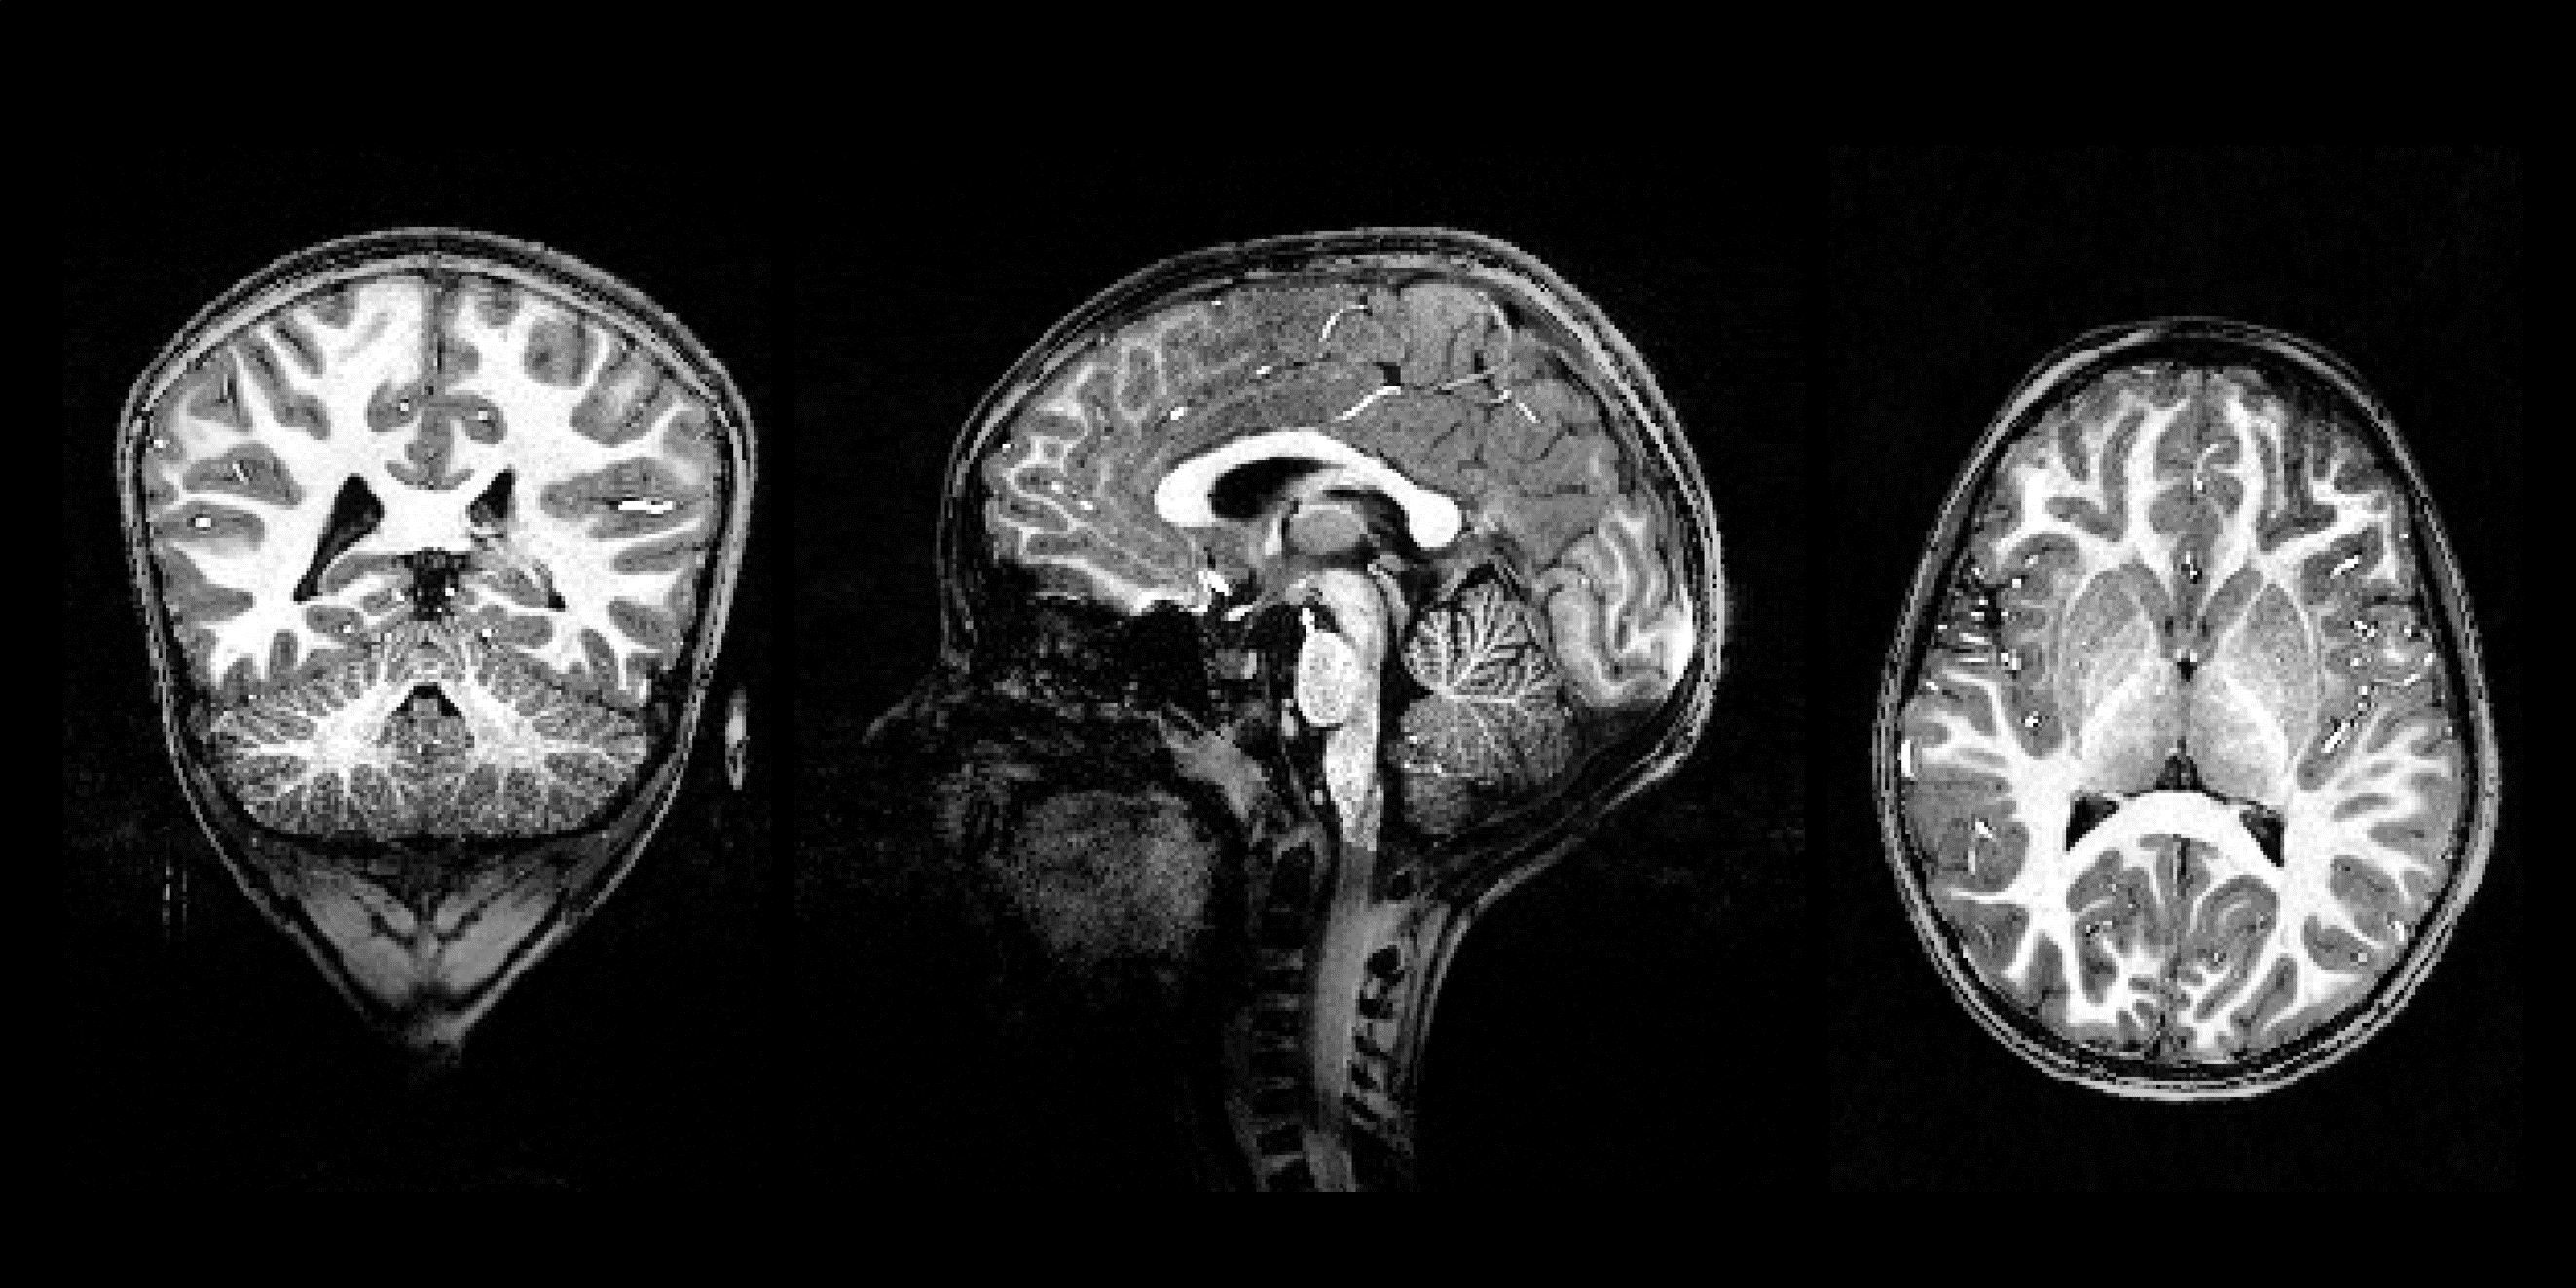

Cerveau enfant IRM 7T sans logo.PNG

Cerveau d'un enfant de 6 ans obtenu avec un IRM à 7T © CEA/NeuroSpin

L’IRM 7T nous donne à présent accès à une richesse d’informations inédite sur le cerveau en développement et les bénéfices attendus sont considérables. Notre compréhension de la mise en place de l’architecture cérébrale (structures de substance grise interconnectées par de la substance blanche) va pouvoir gagner en finesse et relier les échelles macro et microscopiques. Le décryptage du développement des capacités cognitives et des apprentissages va pouvoir s’envisager beaucoup plus à l’échelle individuelle qu’à celle beaucoup plus grossière du fonctionnement moyen d’un groupe. Enfin, on peut s’attendre à la mise en évidence de nouveaux marqueurs pathologiques utiles dans le domaine du soin, des applications étant d’ores et déjà envisagées, comme par exemple l’amélioration de la détection des petites malformations du cortex responsables d’épilepsies débutant dans l’enfance qui peuvent bénéficier d’une intervention chirurgicale curatrice d’autant plus efficacement que la malformation est précisément localisée.

« Grâce au 7T, nous allons mieux comprendre comment les fonctions cérébrales se construisent, sont perturbées, et se réorganisent chez l’enfant. Dans les troubles du neurodéveloppement, cette richesse d’information ouvre la voie à une approche plus individualisée, en tenant compte de la singularité de chaque trajectoire cérébrale développementale. »

Jessica Dubois, chercheuse Inserm à NeuroSpin et à l’Institut Robert-Debré du Cerveau de l’Enfant.